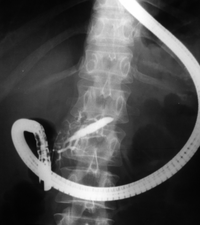

Endoscopic retrograde cholangiopancreatography (ERCP) is a technique that combines the use of endoscopy and fluoroscopy to diagnose and treat certain problems of the biliary or pancreatic ductal systems. Through the endoscope, the physician can see the inside of the stomach and duodenum, and inject a contrast medium into the ducts in the biliary tree and pancreas so they can be seen on radiographs.

The patient is sedated or anaesthetized. Then a flexible camera (endoscope) is inserted through the mouth, down the esophagus, into the stomach, through the pylorus into the duodenum where the ampulla of Vater (the union of the common bile duct and pancreatic duct) exists. The sphincter of Oddi is a muscular valve that controls the opening to the ampulla. The region can be directly visualized with the endoscopic camera while various procedures are performed. A plastic catheter or cannula is inserted through the ampulla, and radiocontrast is injected into the bile ducts and/or pancreatic duct. Fluoroscopy is used to look for blockages, or other lesions such as stones.

When needed, the opening to the ampulla can be enlarged by a cut (sphincterotomy) with an electrified wire called sphincterotome and access into the bile duct obtained so that gallstones may be removed or other therapy performed.

Other procedures associated with ERCP include the trawling of the common bile duct with a basket or balloon to remove gallstones and the insertion of a plastic stent to assist the drainage of bile. Also, the pancreatic duct can be cannulated and stents be inserted. The pancreatic duct requires visualisation in cases of pancreatitis.